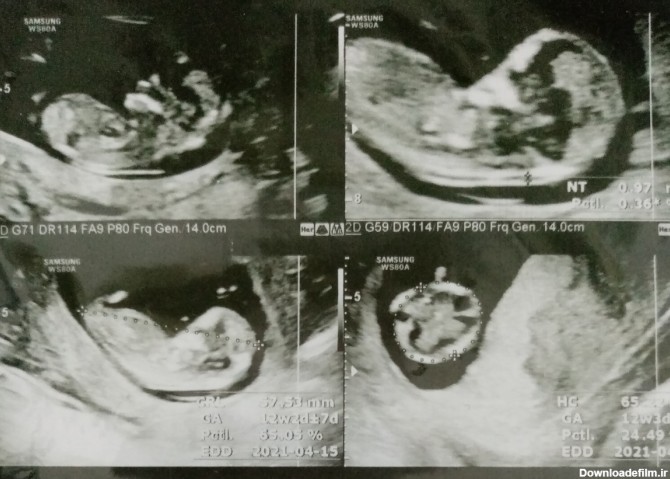

سلام دوستان.میتونید جنسیت رو تشخیص بدین با جمجمه نوزاد؟ شبیه پسر پسر پسره منم یه هفته دیگه سونو دارم😍

کسی میتونه از رو جمجمه بگه نی نی چیه پسر چطوری تشخیص میدی هر چی حدس بزنن ممکنه اشتباه باشه اگه عجله داری ۱۶ هفته سونو برو دکتر نگفت احتمالا دختره یا پسر

هر کسی واقعا بلده و همیشه جوابش درست بوده جنسیت نی نی من رو از سونوی nt بگه لطفاً...میدونم باید صبر کنم واسه آنومالی اما چه کنم که بعد از سال مامان شدم و صبر ند